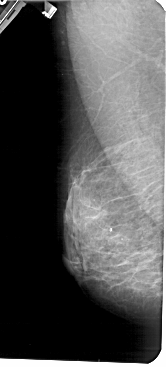

A_1425_1.RIGHT_MLO

LEFT_MLO LINES 5491 PIXELS_PER_LINE 2476 BITS_PER_PIXEL 12 RESOLUTION 43.5 NON_OVERLAY